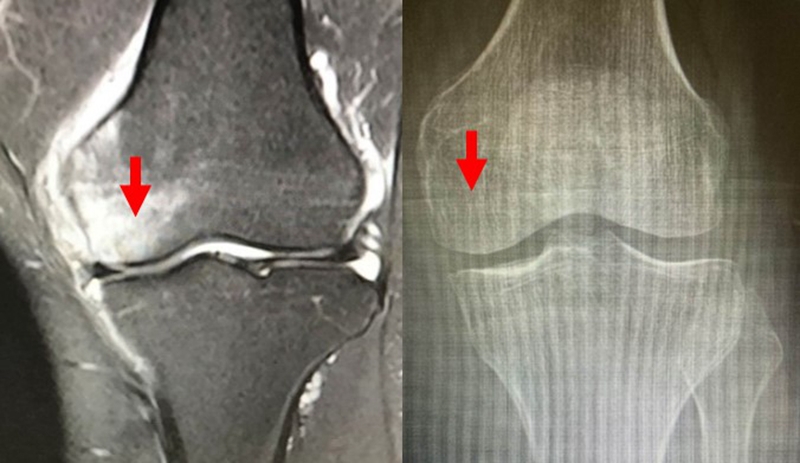

X线+MRI:通过测量正位X线片和MRI判断坏死区域的大小。

目前SONK诊断最常用的分期方法是1979年Koshino提出的分期法。Koshino分期基于临床和影像学的结果,将SONK分为四个阶段:

Ⅰ期:患者有膝关节症状,但影像学正常;

Ⅱ期:X线显示负重区变平,软骨下信号升高,周围有骨硬化;

Ⅲ期:受影响区域扩大和软骨下塌陷;

Ⅳ期:病变周围骨硬化和髁突周围骨赘形成的退行性阶段。

1979年Koshino分期